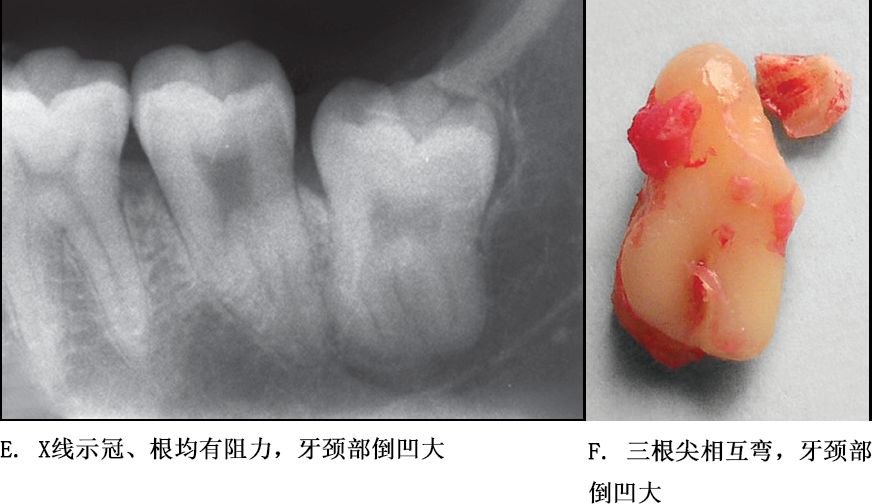

牙根阻力以多根牙、根分歧过大、特长根、U形根、牙颈部倒凹大者阻力较大根尖区以近中弯曲、多向弯曲、根尖肥大者牙根阻力较大。

根部阻力较小的智齿形态

单根牙、根分叉不大者、合并根、融合根、特短根、锥形根阻力较小。若根尖区向远中弯曲、无弯曲或根尖未形成,则阻力也较小。